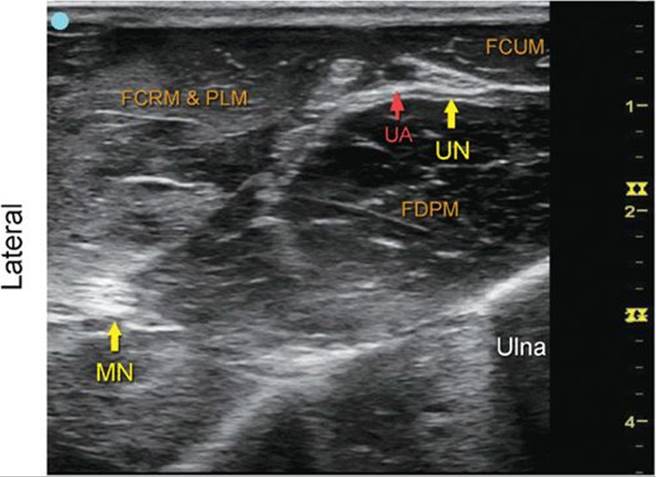

Median and Ulnar Nerve at the Midforearm

FIGURE 7.26.1A Ultrasound transducer position to image the median and ulnar nerve at the midforearm.

FIGURE 7.26.1B Ultrasound image of the median and ulnar nerve at the midforearm.

FIGURE 7.26.1C Labeled ultrasound image of the median and ulnar nerve at the midforearm.

FIGURE 7.26.1D Labeled cross-sectional anatomy of the median and ulnar nerve at the midforearm.

Abbreviations: MN, Median Nerve; UN, Ulnar Nerve; UA, Ulnar Artery; FDPM, Flexor Digitorum Profundus Muscle; FCUM, Flexor Carpi Ulnaris Muscle; FCRM, Flexor Carpi Radialis Muscle; PLM, Palmaris Longus Muscle.